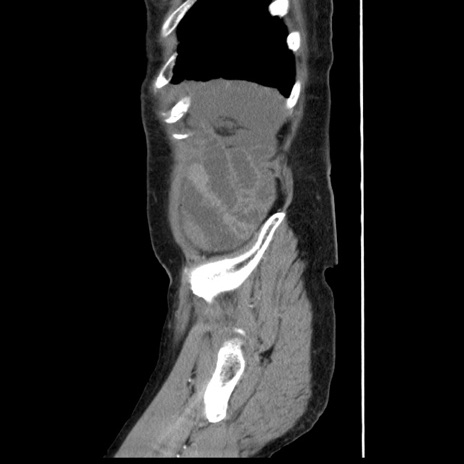

症例1(矢状断像)

【症例】80歳代女性

【主訴】腹痛

【現病歴】8時間前から腹痛あり来院。

【既往歴】糖尿病、脂質異常症、子宮体癌にて子宮全摘術

【身体所見】意識清明・会話良好だが腹痛で苦悶様、全腹部にわたって反跳痛と圧痛あり

【データ】WBC 13600、CRP 0.14、LDH 224、CK 90